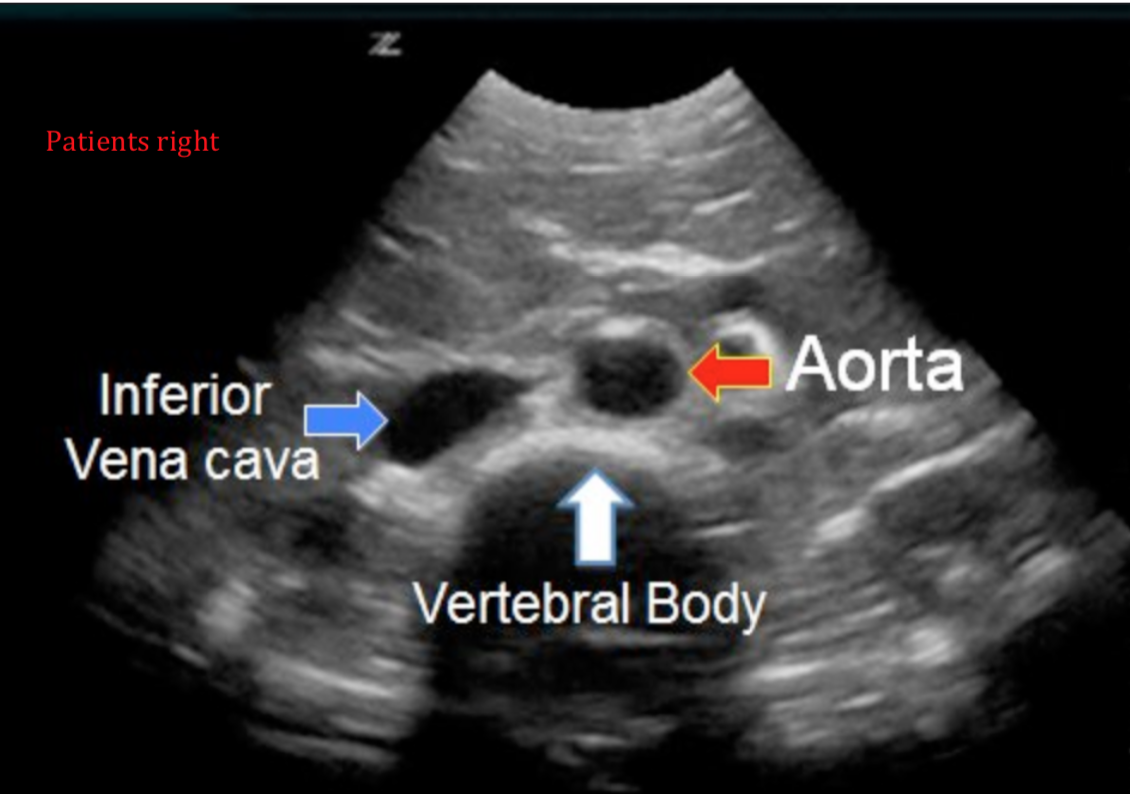

Start at the epigastrium in the transverse plane (short axis of the aorta) with the probe marker to the patients right side. Use the liver as a sonic window to help attain image.

• Identify the vertebral body

• Identify the aorta:

• Superficial to the vertebral body slightly to the patients left

• To the right of the midline on the screen (check probe marker orientation)

• Circular in the short axis

• Pulsatile

• Thick walled

• Identify the IVC

• To the left of the midline on the screen - the patients right side

• Less circular

• Usually displays collapsability with respiration